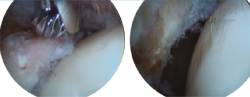

Retiraremos los osteofitos con una fresa desde la unión capsulolabral para movernos más cómodos y seguiremos con la resección del os labrale, osteofito o labrum calcificado (Figura 3).

Figura 3. Paciente con osteofito en el reborde acetabular (imagen izquierda). Resección del osteofito en el reborde acetabular (imagen derecha).

Un gesto añadido que podemos hacer, sin conocer exactamente la repercusión clínica del mismo, es la retirada del osteofito central con fresas o material cortante curvo (Figura 4).

Figura 4. Paciente con osteofito central acetabular (imagen izquierda). Resección del osteofito central (imagen derecha).